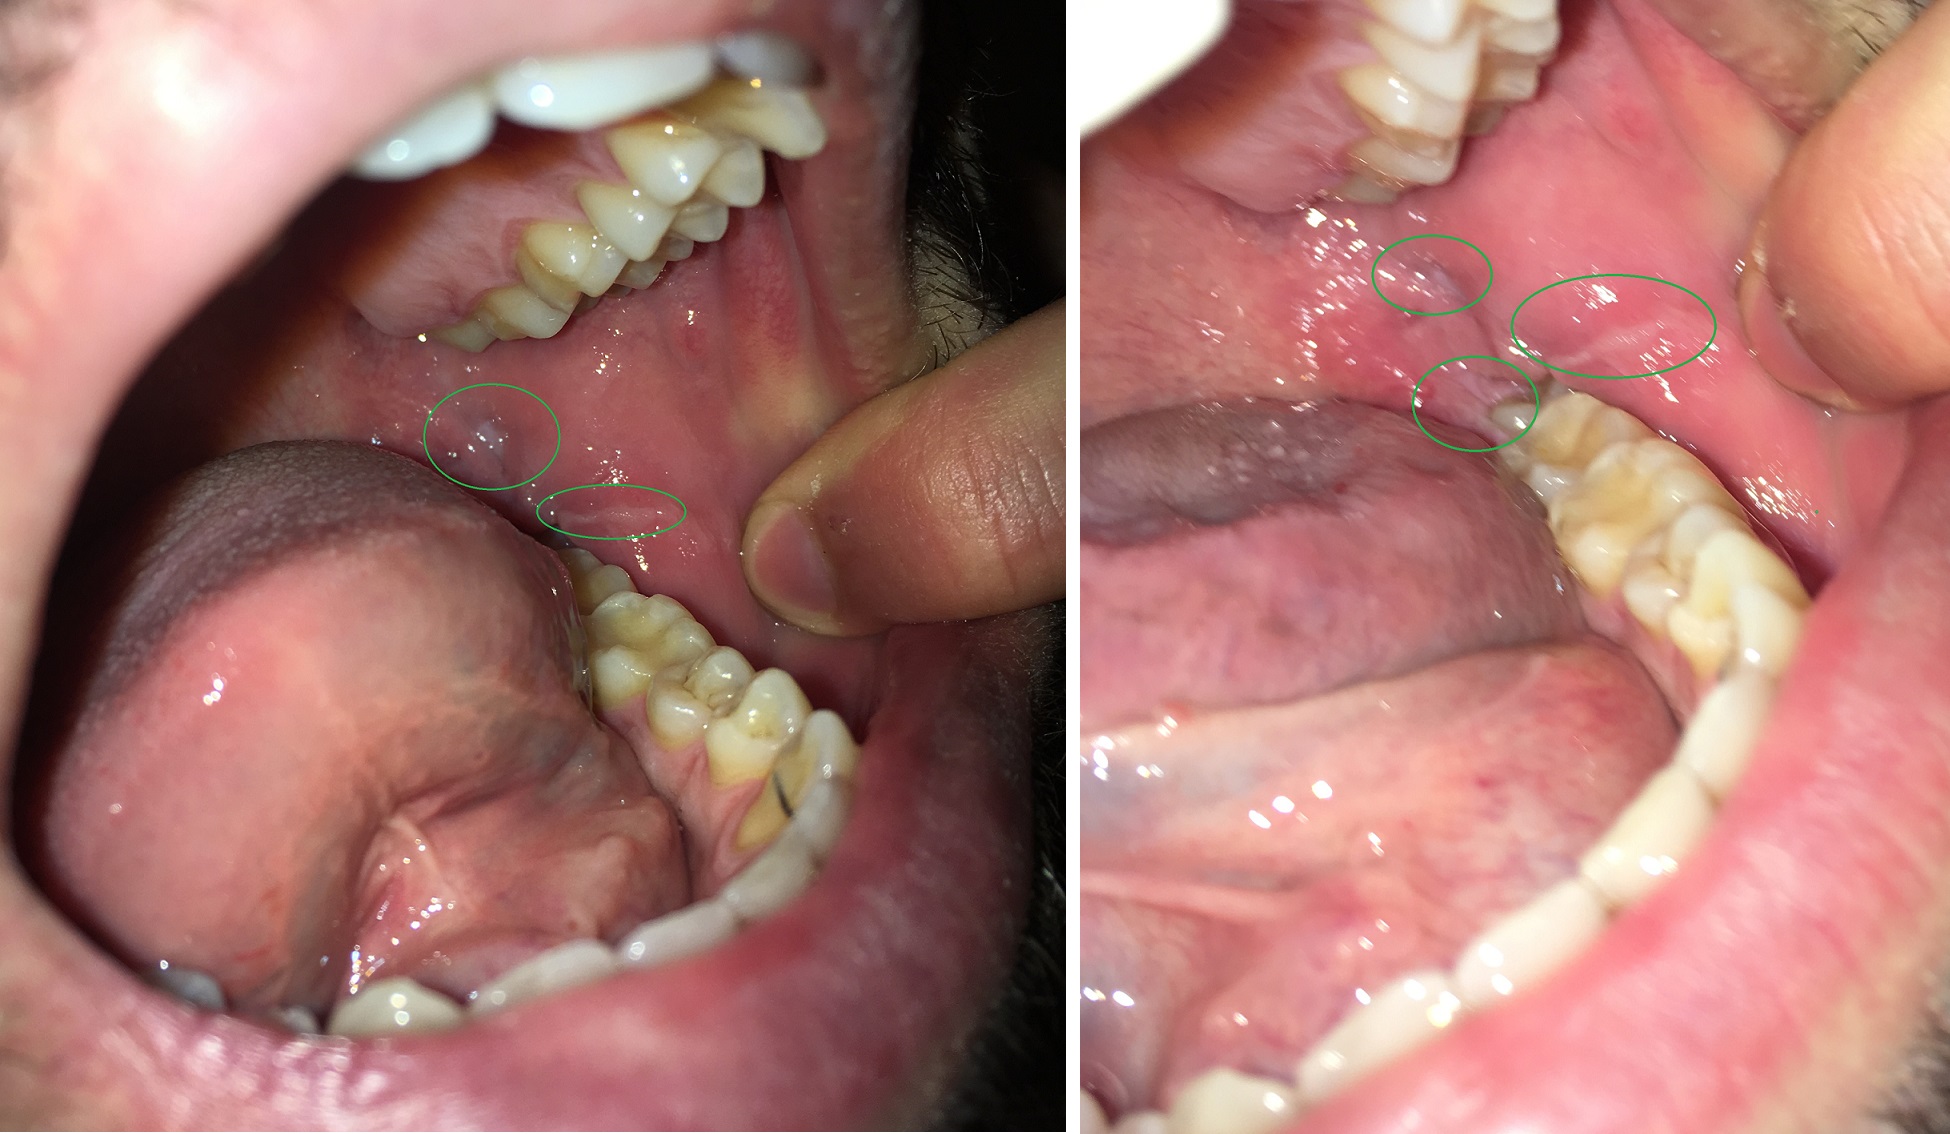

Hoi allemaal, sinds een tijdje heb ik geregeld last van witte onstoken plekjes op mijn tandvlees (de ene een ronde wite plek en de ander een soort van witte streep).

Nu heb ik sinds een paar dagen een terugkeer van dit maar in een wat meer pijnlijke vorm. Het lijkt overgezaaid te zijn naar onderkant kies/kaak. (Het doet pijn als ik mijn mond helemaal opentrek). Wat kan dit in hemelsnaam zijn: Aften, Parodontitis, Gingivitis of toch MONDKANKER...? HELP ME OUT PLEASE.. Bekijk de foto in de bijlage